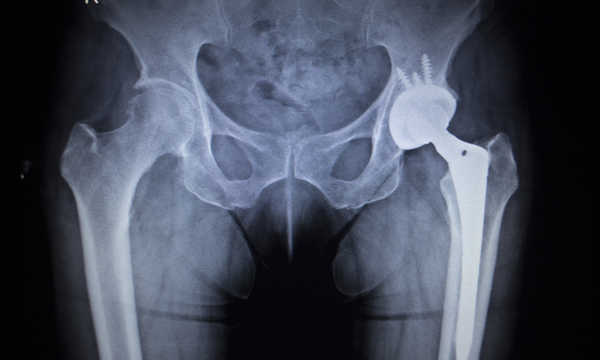

Dolegliwości w późnej fazie utrudniają normalne funkcjonowanie i chodzenie – na tyle, że konieczne jest podpieranie się podczas chodu. Często dochodzi wtedy także do zaburzeń w sylwetce chorego. Gdy borykamy się z takimi objawami najlepiej niezwłocznie skierować się na badanie RTG, które pomoże dokonać trafnej diagnozy schorzenia i określić stopień schorzenia. W praktyce klinicznej RTG jest zwykle badaniem pierwszego wyboru przy podejrzeniu choroby zwyrodnieniowej biodra. To pozwoli ocenić, czy konieczny będzie zabieg operacyjny i wymiana stawu.

Zwyrodnienie może w późniejszym etapie doprowadzić nawet do znacznego ograniczenia sprawności. W takim przypadku częstą koniecznością staje się przeprowadzenie zabiegu wszczepienia endoprotezy stawu biodrowego, czyli sztucznego stawu biodrowego.